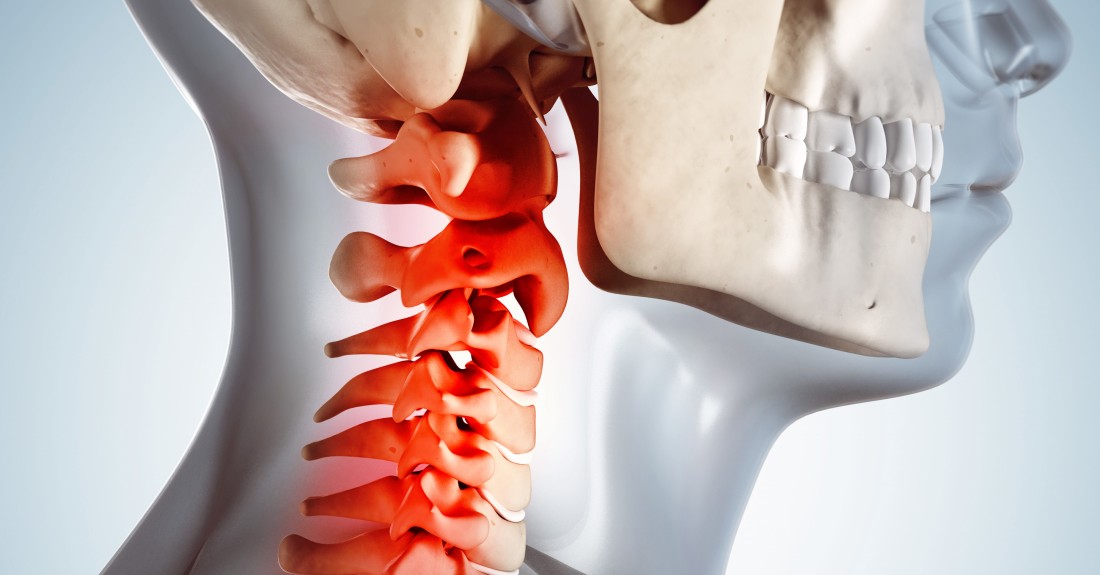

오늘은 목디스크 증상에 대해 확인해 보도록 하겠습니다.

목디스크 증상 -목 통증

목의 디스크가 손상이 일어나서 부근 신경을 자극하여 심각한 통증을 같이할수 있는데요 통증은 상식적으로 목의 한쪽 면에 유발되며, 어깨나 팔까지 타나날 수 있습니다.